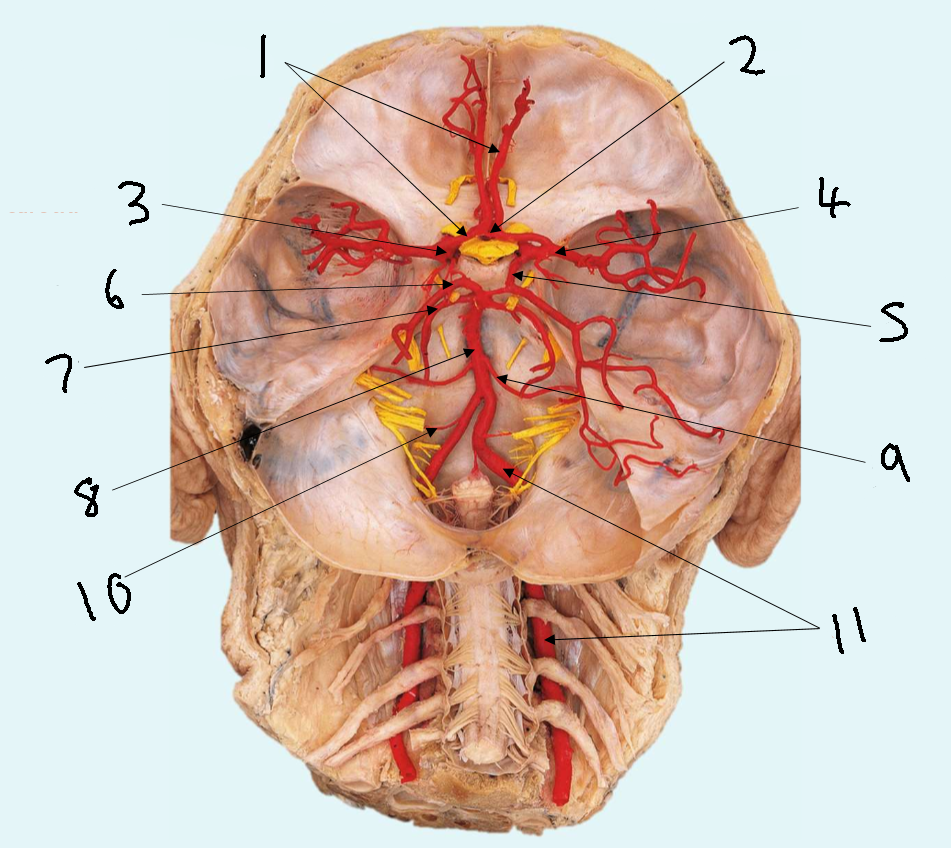

What is 1?

anterior cerebral artery

What is 2?

anterior communicating artery

What is 3?

internal carotid artery

What is 4?

posterior communicating artery

What is 5?

posterior cerebral artery

What is 6?

basilar artery

What is 7?

vertebral artery